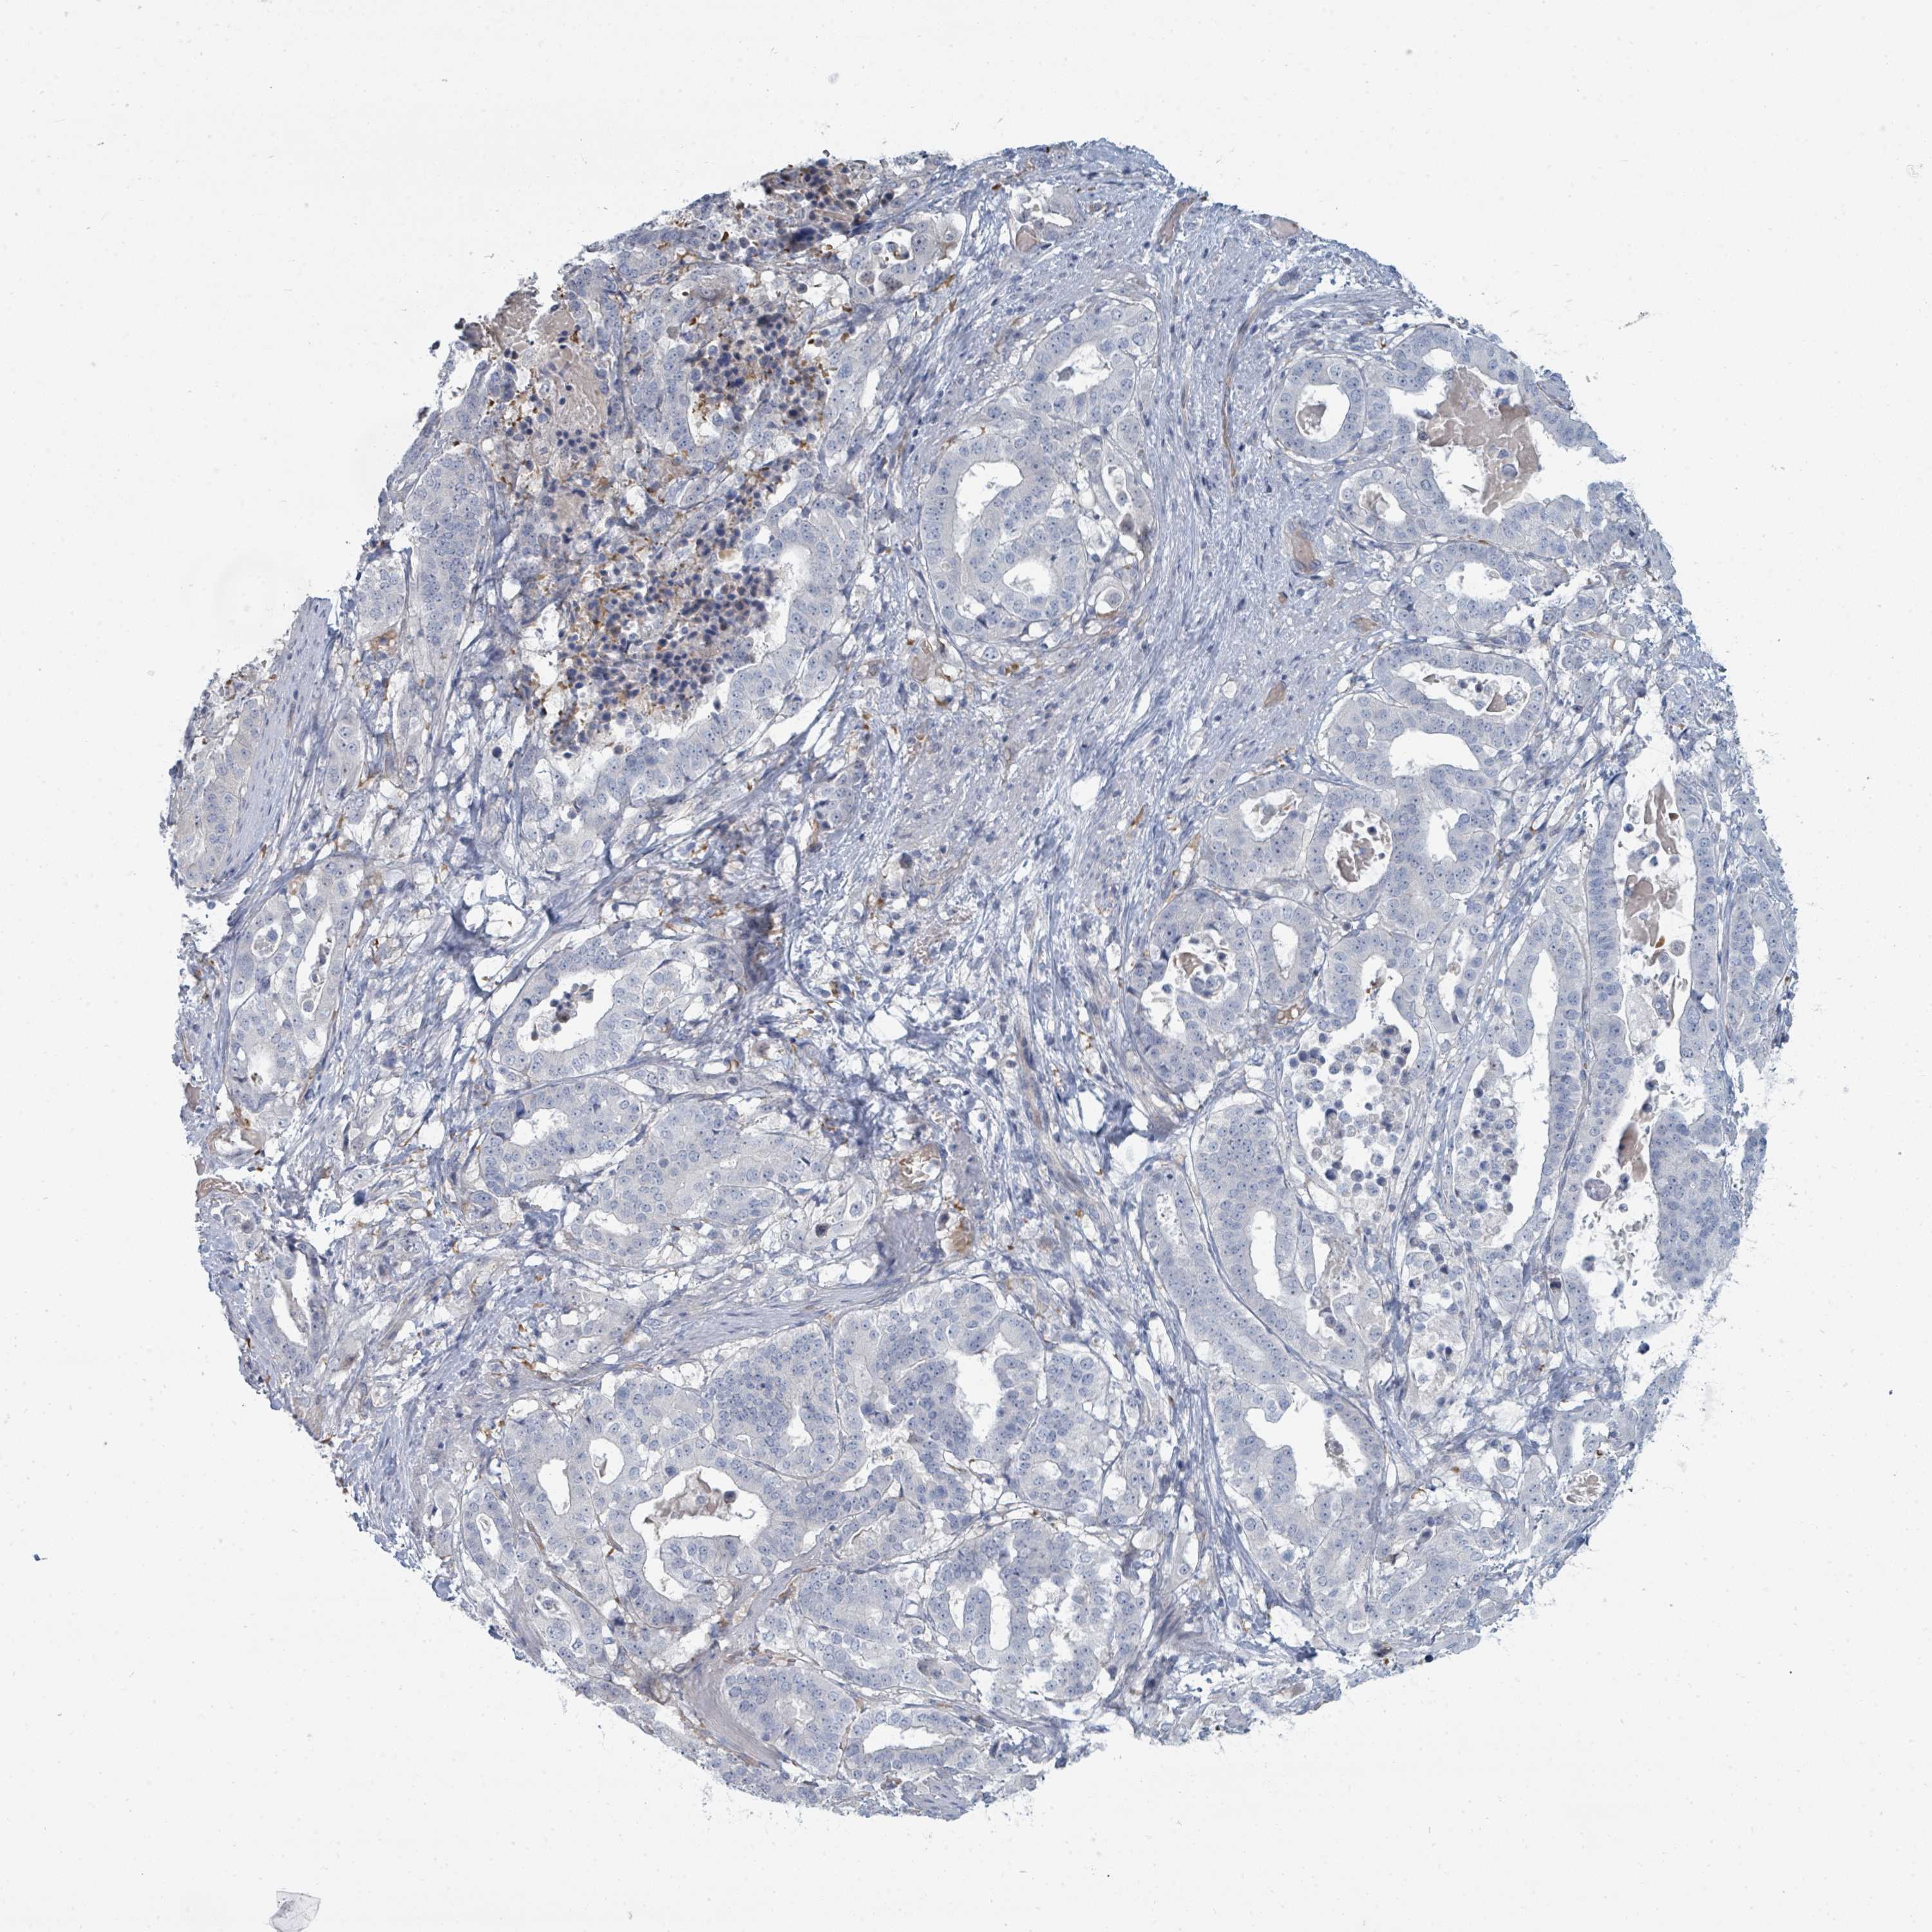

STOMACH CANCER - Protein expressioni

A mouse-over function shows sample information and annotation data. Click on an image to view it in a full screen mode. Samples can be filtered based on level of antibody staining by selecting one or several of the following categories: high, medium, low and not detected. The assay and annotation is described here.

Note that samples used for immunohistochemistry by the Human Protein Atlas do not correspond to samples in the TCGA dataset.

Antibody stainingi

Antibody staining in the annotated cell types in the current human tissue is reported as not detected, low, medium, or high, based on conventional immunohistochemistry profiling in selected tissues. This score is based on the combination of the staining intensity and fraction of stained cells.

Each image is clickable and will lead to virtual microscopy that enables deeper exploration of all samples and also displays staining intensity scores, fraction scores and subcellular localization as well as patient and tissue information for each sample.

Antibody HPA050821

Staining

High

Medium

Low

Not detected

Intensity

Strong

Moderate

Weak

Negative

Quantity

>75%

75%-25%

<25%

None

Location

Nuclear

Cytoplasmic/membranous

Cytoplasmic/membranous,nuclear

Adenocarcinoma, NOS